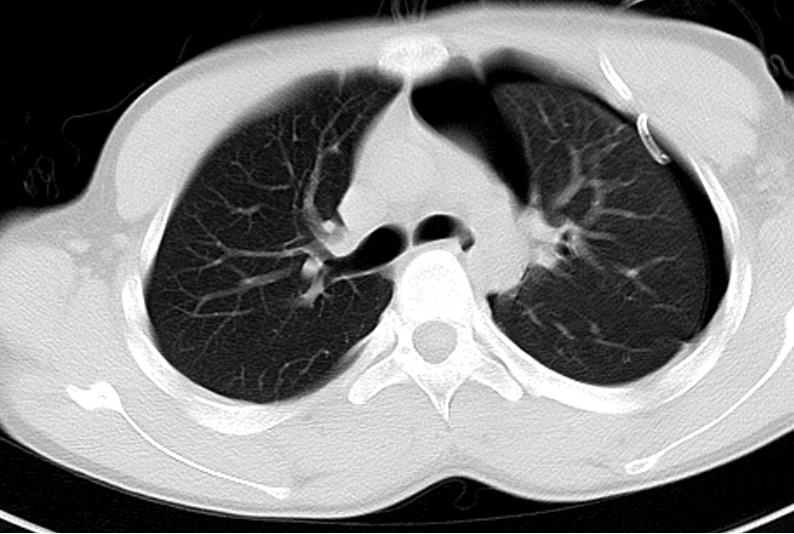

下一步行胸部CT检查:

结合胸部CT所示,可见明显的肺大泡(肺尖处)和气胸。遂在全麻下行胸腔镜下左上肺大泡切除术+胸膜粘连松解术+胸腔闭式引流术:患者麻醉成功后,取右侧90°卧位,常规消毒铺巾,于左腋前线第4肋间作一约5厘米的小切口,钝性分开胸壁肌层及壁层胸膜,经小切口置入套管,胸腔镜进入左胸腔,探查见:左上肺叶肺尖部一个肺大泡,约3.0cm×2.0cm,大泡与壁层胸膜粘连,余肺部未见肺大泡。术中诊断:左上叶肺大泡。在胸腔镜观察下,以电钩分离胸腔粘连;分别导入腔镜用肺钳及60#endo-GIA,提起左肺上肺大泡,以一把60#endo-GIA在肺大庖基底部边缘钳夹后,切除肺大庖,取出标本,检查切缘为肺组织。检查左胸腔见无异常渗血及气泡溢出,于左腋前线第4肋间放置胸闭式引流管各一条且固定于皮肤。清点纱布器械无误,逐层缝合左胸切口各层。术程顺利,术中出血少许,未输血。